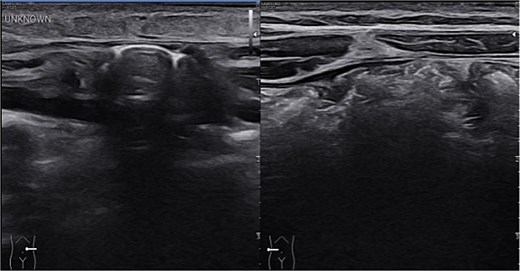

Sonographic imaging comparing left and right upper quadrant. On the left side intestinal content is seen within the hernia sac. On dynamic sonography peristalsis was apparent.